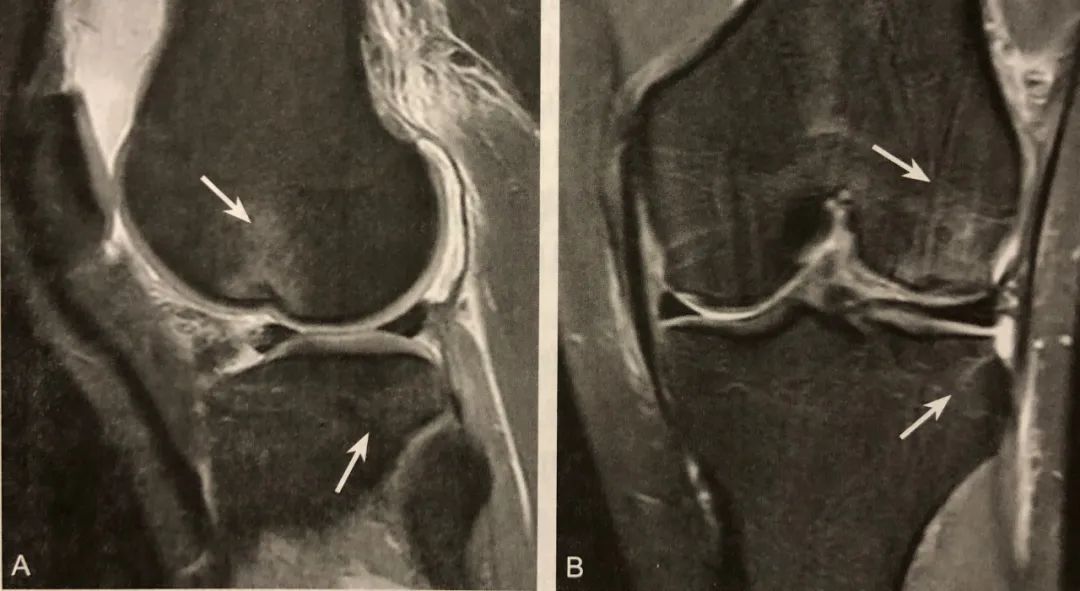

阅片要点:

1. 内侧半月板桶柄状撕裂间接征象;

2. 在 MRI 矢状位观察;

3. 典型表现为两条近似平行的弧形低信号带;

4. 后上方者为后交叉韧带,前下方者为撕裂的半月板内缘碎片;

5. MRI 诊断注意结合病史和排外相关变异。